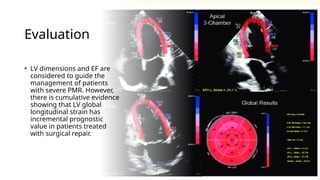

Evaluation

• LV dimensions and EF are

considered to guide the

management of patients

with severe PMR. However,

there is cumulative evidence

showing that LV global

longitudinal strain has

incremental prognostic

value in patients treated

with surgical repair.